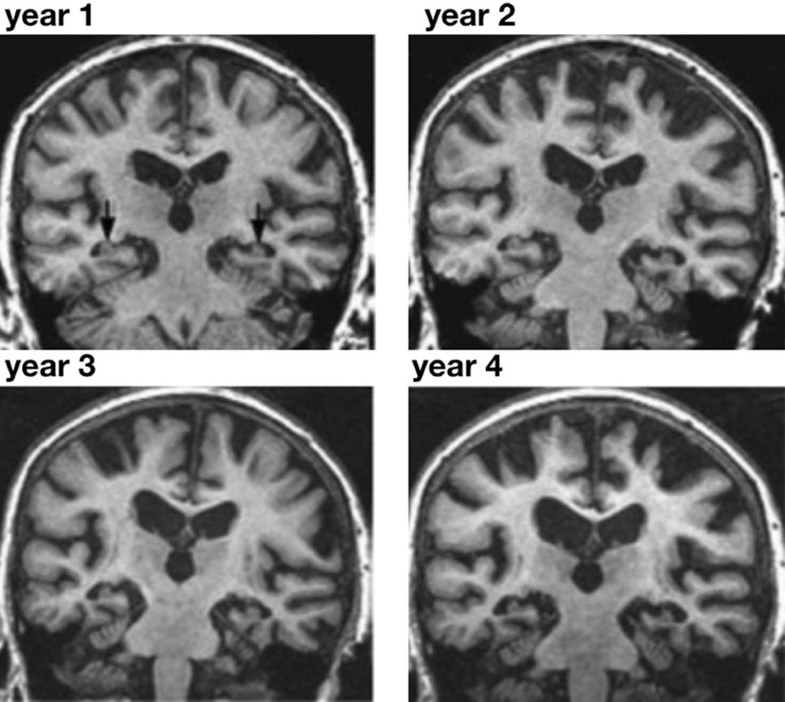

From multiple-sclerosis-research.blogspot.com

Multiple Sclerosis Research Brain shrinking occurs early in MS Signs Brain Is Shrinking Different conditions cause brain atrophy,. Brain atrophy, or cerebral atrophy, is a condition in which the brain or regions of the brain decrease or shrink in size. Find out what to expect and how you can maintain your brain health. Cerebral atrophy is the loss of brain cells, called neurons, and their electrochemical connectors, called synapses. Brain atrophy can affect. Signs Brain Is Shrinking.